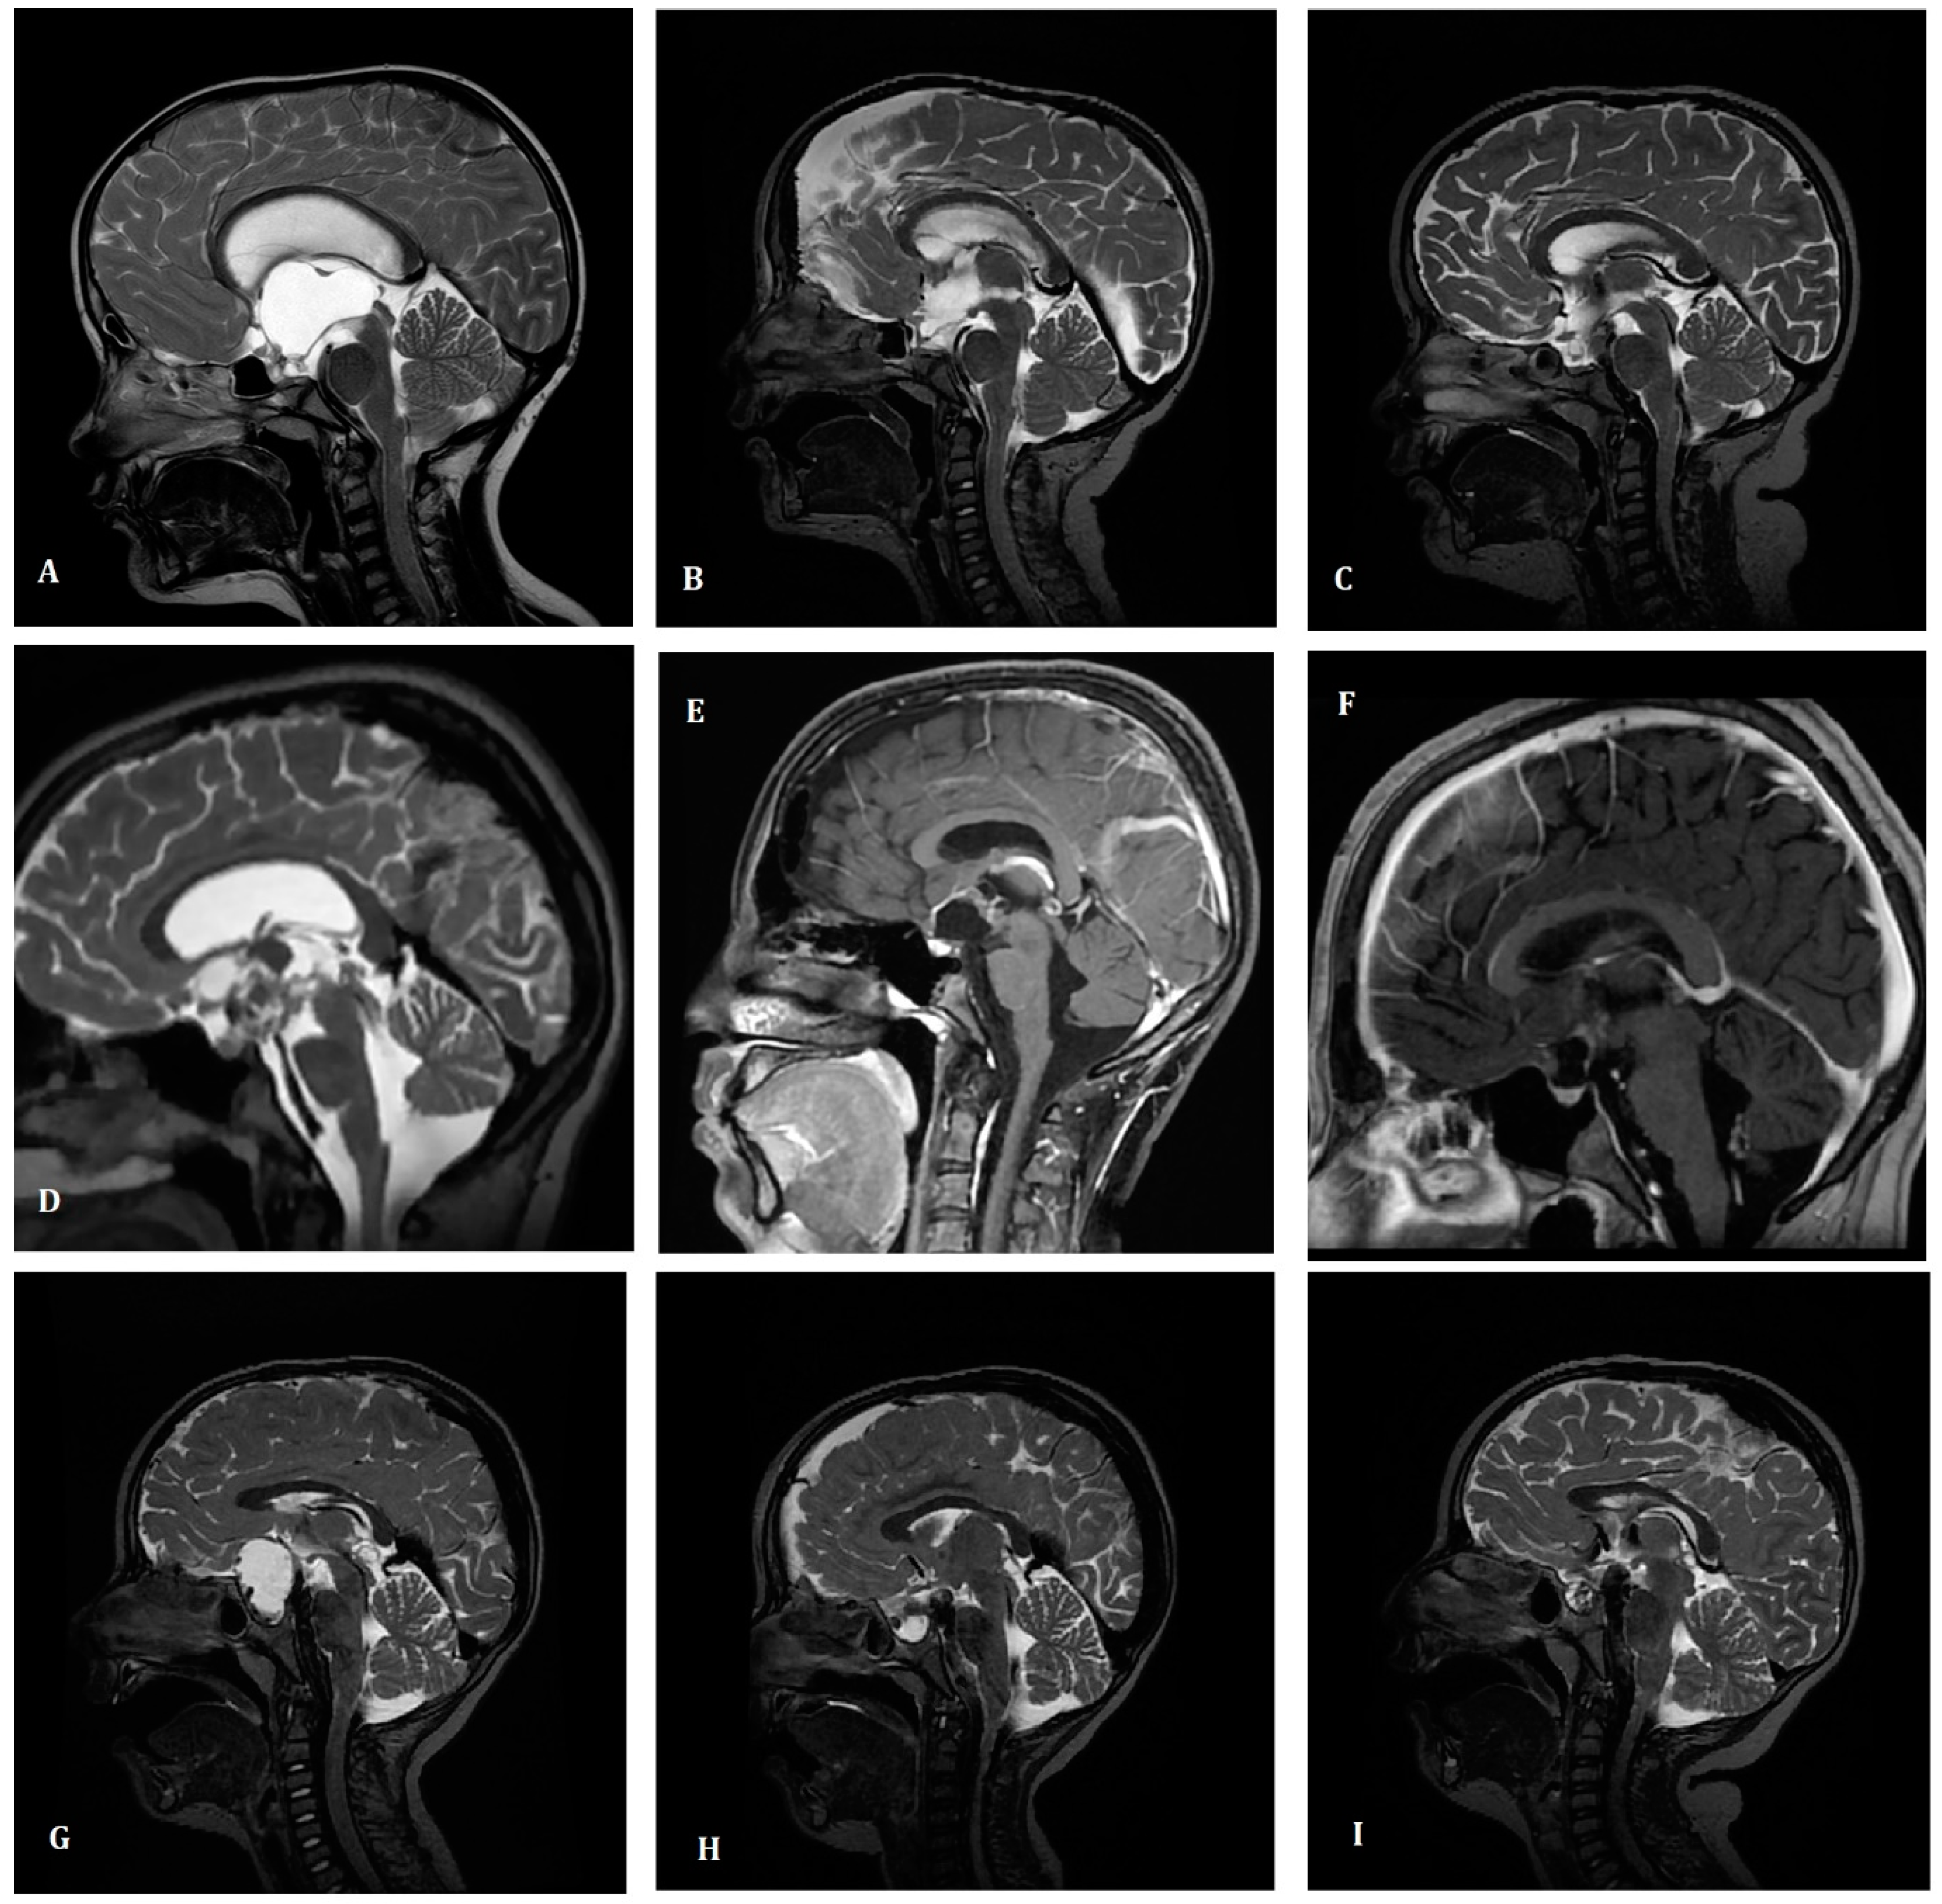

The study group consisted of 56 consecutive patients. In Table 1, we present the comparison of the patients’ and treatment characteristics based on the year of primary treatment applied. At the time of diagnosis, the most common symptoms were: visual deficits (46%), endocrine deficits (29%), headaches (61%), vomiting/nausea (39%), disturbances of consciousness (9%), epilepsy (4%), or other (27%). Two patients (4%) had tumor diagnosed incidentally in a brain MRI performed due to other reasons. Most of the patients had a diagnosis based on only MR (36%) or MR with CT (43%) except for those treated in the early years of the study (21%). The mean tumor dimensions at the time of diagnosis were 32 × 30 × 28 mm (ranged from 7 to 93 mm in the largest dimension)—see example in Figure 1. The most common primary symptoms were headaches (61%), visual deficits (46%), and nausea or vomiting (39%). In 16 cases, endocrine deficits were present before the tumor diagnosis, with the most common being related to a low level of growth hormone (GH) and luteinizing hormone/follicle-stimulating hormone (LH/FSH) present in 7 and 6 cases, respectively.

Figure 1. Examples of magnetic resonance imaging of treated patients. Case 1 (upper row) Six-year old boy treated with partial surgery. Conventionally fractionated irradiation was applied due to the progression of the size of the tumour. Magnetic resonance imaging (MRI) performed before the surgery (A), 3 days after the surgery (B) and six months later (C). Initial tumour dimensions were 56 × 49 × 39 mm and patient suffered from preoperative visual deficits. After the surgery endocrine deficits were diagnosed. After the irradiation the size of tumour is stable and no complications were present. Currently he is alive in follow-up and increase in body mass index is observed. Case 2 (middle row) Fourteen-year old boy treated with partial surgery and postoperative conventionally fractionated irradiation. Magnetic resonance imaging (MRI) performed before the surgery (D), 2 days after the surgery (E) and three and half months later (F). Initial tumour dimensions were 35 × 30 × 34 mm and patient suffered from preoperative headaches, visual deficits and increase in weight. After the surgery endocrine deficits were diagnosed. After the irradiation the size of tumour is stable and no complications were present. Currently he is alive in follow-up. Case 3 (lower row) Four-year old boy treated with partial surgery. Single fraction (16 Gy) of stereotactic radiotherapy was applied due to the progression of the size of the tumour. Magnetic resonance imaging (MRI) performed before the surgery (G), 7 days after the surgery (H) and one year later (I). Initial tumour dimensions were 23 × 36 × 28 mm and patient suffered from preoperative visual deficits (blindness of left eye) and endocrine deficits. After the surgery endocrine deficits were diagnosed. After the irradiation the size of tumour is stable and no complications were present. Currently he is alive in follow-up.